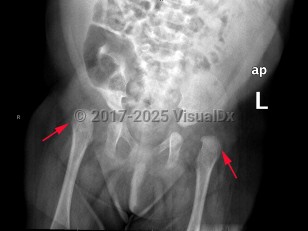

Developmental dysplasia of the hip in Infant/Neonate

A spectrum of developmental abnormalities of hip joint dislocation or subluxation of the acetabulum and proximal femur (head), typically diagnosed in infants and children. Most often unilateral, but may be bilateral (20%). Common signs and symptoms include hip instability, pain, limited range of motion, abnormal gait, and limping. It may be associated with breech birth, family history, or social practice of swaddling. Some neuromuscular disorders may be associated with hip dysplasia. Early intervention decreases lasting and progressive damage, limiting functional disability and preventing early-onset osteoarthritis. Many cases of infant hip instability will gradually stabilize.